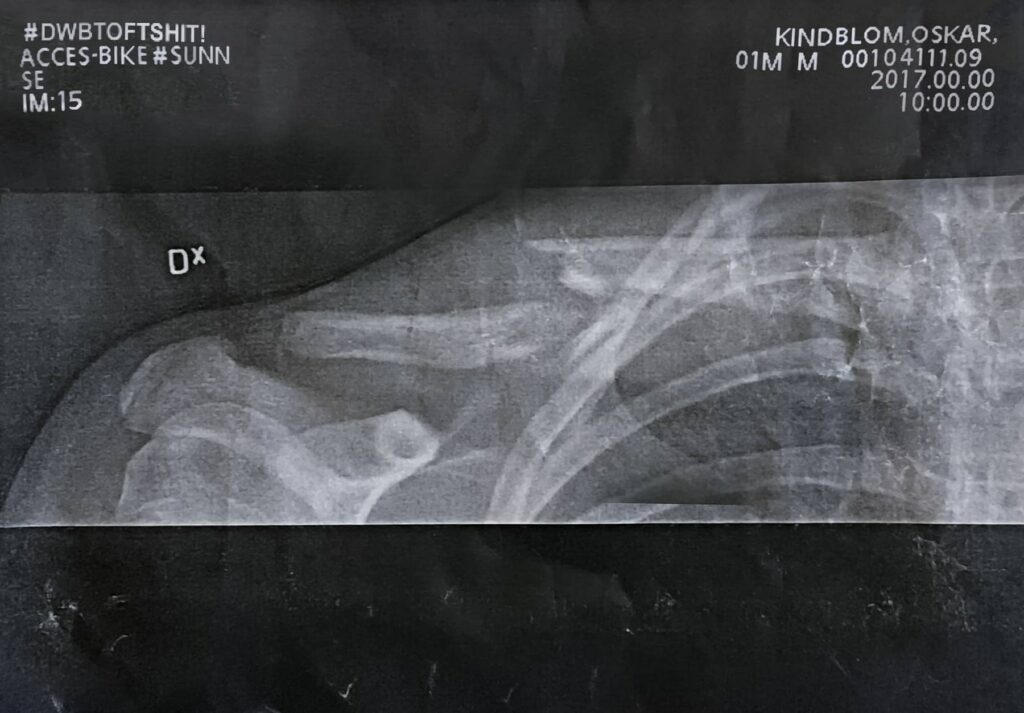

Oskar crashed hard during practice

About two weeks ago our ambassador Oskar made a hard crash on the track in Kungsbacka. Unfortunately, he broke his collarbone and have to rest from his precious bike a couple of weeks.

He felt a bit down but we are not worried at all. With his skills and flow, he will be hitting the tracks as normal as soon as he’s back on the bike!